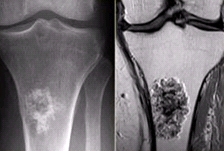

內(nèi)生軟骨瘤